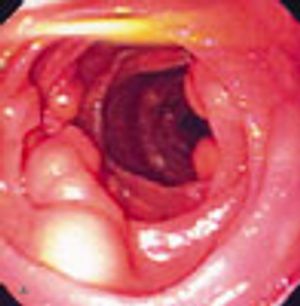

A 72-year-old man presented after several months of dyspepsia and 1 day of hematemesis. He was not taking NSAIDs.